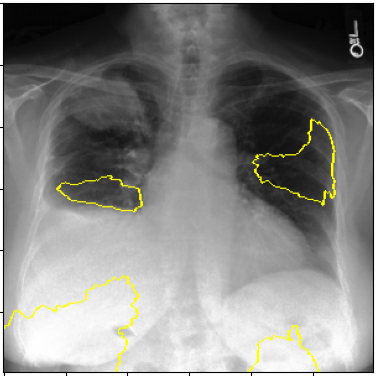

3.3 Interpretability

Post-Hoc Comparisons. We compare our concept-based explanations to post-hoc XAI techniques LIME and SHAP, applied to the baseline InceptionV3 model. The image explanations generated by these techniques disagree with each other and the medical ground truth. We show an example of this observation in Figure 7, where both techniques fail to capture the large mass in the X-ray, and highlight irrelevant regions such as areas outside of the lung as incorrectly important to the classification decision. In contrast, our approach correctly identifies the presence of a mass. More examples are shown in Figure 10.

Refer to caption

(a) Ground Truth

(b) LIME

(c) SHAP

(d) CXR-LLaVA Generated Report

(e) Our Approach

Figure 7: Example of our explanation approach outperforming LIME, SHAP and CXR-LLaVA. Ground truth (a) is a “Large right upper zone mass". LIME (b) and SHAP (c) fail to capture the mass in the X-ray. Most important image regions are bounded by yellow for LIME, and shown in more vibrant green for SHAP. CXR-LLaVA (d) generates a report which wrongly describes the image as non-cancerous. Our approach (e) correctly identifies the presence of a mass.

(a) Ground Truth 1

(b) Ground Truth 2

(c) Ground Truth 3

(d) Ground Truth 4

(e) LIME 1

(f) LIME 2

(g) LIME 3

(h) LIME 4

(i) SHAP 1

(j) SHAP 2

(k) SHAP 3

(l) SHAP 4

Figure 10: Examples of LIME and SHAP explanations failing to capture the medical ground truth of a cancerous chest X-ray, while also generating conflicting explanations. Ground truth (a,b,c,d) is shown as red squares. Most important regions are bounded by yellow for LIME (e,f,g,h) and shown as more vibrant green for SHAP (i,j,k,l).